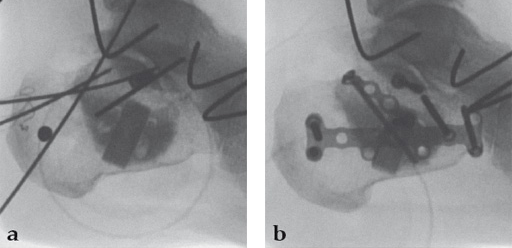

Case 2: A 38-year-old man sustained a lateral tibia plateau fracture (Müller AO Classification 41-B.3/Schatzker type II).

(Case provided by Michiel Verhofstad, Tilburg, The Netherlands)

After opening the lateral wedge, the osteochondral fragment was reduced and maintained with two K-wires. A gap beneath this fragment was left. Subsequently, a 3.2 mm hole was drilled in the lateral wedge using an inside-out technique. Then the lateral fragment was reduced. A 3-hole buttress plate, followed by two subchondral compression screws were used for final fracture fixation. Finally, Norian drillable was injected in the gap through the predrilled hole. Weight bearing was started after 6 weeks. At 6 months the fracture had healed anatomically and the patient was complaint-free.